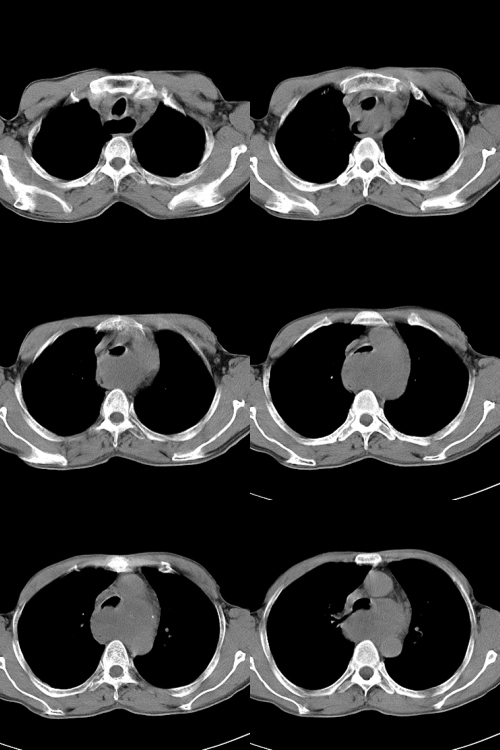

以下是引用zsl6918在2009-2-7 7:38:00的发言:[br]恶性度极高的肺癌,肺门及纵隔淋巴结转移。

以下是引用余辉在2009-2-7 8:29:00的发言:[br]考虑左下肺周围型肺癌伴肺门、纵隔淋巴转移及右肺转移